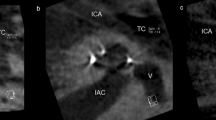

Postoperative imaging was performed using a DynaCT-equipped Axium Artis dTA angiography unit (Siemens Co., Erlangen, Germany) with a digital flat-panel detector [3, 7]. Two experienced head and neck surgeons and two head and neck radiologists independently analyzed the scans regarding scalar electrode position (ST versus SV insertion, intracochlear dislocation, angular insertion depth) and cochlear size (diameters in length and width) and used Impax 6 from Agfa Healthcare for reconstruction. The scans were not evaluated by the surgeons who, performed the CI surgery but by independent and experienced head and neck surgeons to reduce bias. All included electrode arrays were fully inserted. Cochlear size was evaluated in distance A from the round window to the lateral wall through the modiolus and perpendicular distance B [1, 2, 8]. The angular insertion depth was evaluated between the vectors of distance A and the distance through the bloom artefact of the apical electrode and the modiolus as described before [2, 8, 9]. Dislocation analysis and analysis of scalar position were performed on three-dimensionally reconstructed cross-sectional images as previously described [2, 8], i.e. the 3D-reconstruction could be rotated and browsed in whichever direction the specialists needed to come to their respective conclusion. Every image with discrepancy was reviewed and discussed interdisciplinary until a final agreement and measurement was achieved.

Measuring the specific position of dislocation for each electrode array, we found that the position of dislocation depends on the electrode array itself (see Fig. 4). We measured a significant lower point of dislocation for the CA compared to both the Flex28 (p < 0.00001) and the FlexSoft (p < 0.00001). The point of dislocation is electrode-design specific. Perimodiolar electrode arrays dislocate between 160 and 180° (CA: mean ± SD: 170 ± 25°), whereas straight electrode arrays dislocate between 280° and 330° (Flex28: mean ± SD: 284 ± 87°; FlexSoft: mean ± SD: 330 ± 36°).

We could show that the position of dislocation is electrode-design specific (see Fig. 4) and depends on electrode array design itself. The SSA has a stiff internal stylet and is a lateral wall array. Therefore, the dislocation point is more apical than the dislocation point of the perimodiolar CA. The CA is inserted via an Advance Off–Stylet™ insertion technique and due to its preformed perimodiolar design the point when dislocation might happen is earlier and at approximately 180°. Further studies described the ascending cochlear basal turn at around 180° as sensitive for scalar dislocation [13,14,15]. Aschendorff et al. [7] speculated that perimodiolar electrode arrays may touch the outer cochlear wall at 180° while rotating with an upward direction and being pushed forward, resulting in perforation of the basilar membrane.

Boyer et al. [13] analyzed 61 CBCT scans of 54 patients. Eight perimodiolar electrode arrays and one straight electrode array were described as dislocated. The authors speculated that straight electrode arrays dislocate at approximately 370°, whereas perimodiolar electrode arrays dislocate at around 170°–190°. We can now confirm that the CA dislocates at approximately 170°, corresponding to the ascending part of the cochlear basal turn. Boyer et al. [13] compared only two groups: perimodiolar (CI 512 and CI24RECA) versus straight (FlexSoft, Flex24, Flex28 and FlexStandard) electrode arrays. Whereas their defined perimodiolar group seems to be a homogeneous electrode array cohort (n = 31), the straight electrode array group (n = 30) is not only too small to define angular insertion depth and manner of dislocation but also inhomogeneous, comparing electrode arrays from MED-EL of different lengths and diameters. Furthermore, they neither excluded the CS-inserted electrode arrays nor calculated if there is a statistically relevant effect of RW versus CS or not. We examined the influence of the insertion location and can show that CS does not lead to higher dislocation rates or SV insertions in any of the included arrays. Boyer et al. and Wanna et al. [13, 17] described that straight electrode arrays are more often completely inserted within the ST and hypothesized that straight electrode arrays are more flexible due to the silicon density of the electrode array. Nevertheless, they did not exclude CS-inserted electrode arrays. Additionally, the CA electrode array, which was originally designed for CS approach, was inserted via RW. Rebscher et al. and Souter et al. [18, 19] described that the CA is only designed for CS due to the higher incidence of cochlear trauma in RW approach. They argued that the electrode array may be too close to the lateral wall, which might result in traumatic deflection. Therefore, the insertion of the CA via CS is recommended, even though RW insertions are also possible in exceptions. Table 2 shows that with only a few exceptions, the included CA arrays of our study were not inserted via RW, but in 98% via CS. In conclusion, this study extends the previous knowledge of angular insertion depth, dislocation behavior and the influence of cochlear morphology. Furthermore, we could measure defined angular insertion depth and dislocation data of each included electrode array and could show that each electrode array has a specific position of dislocation.